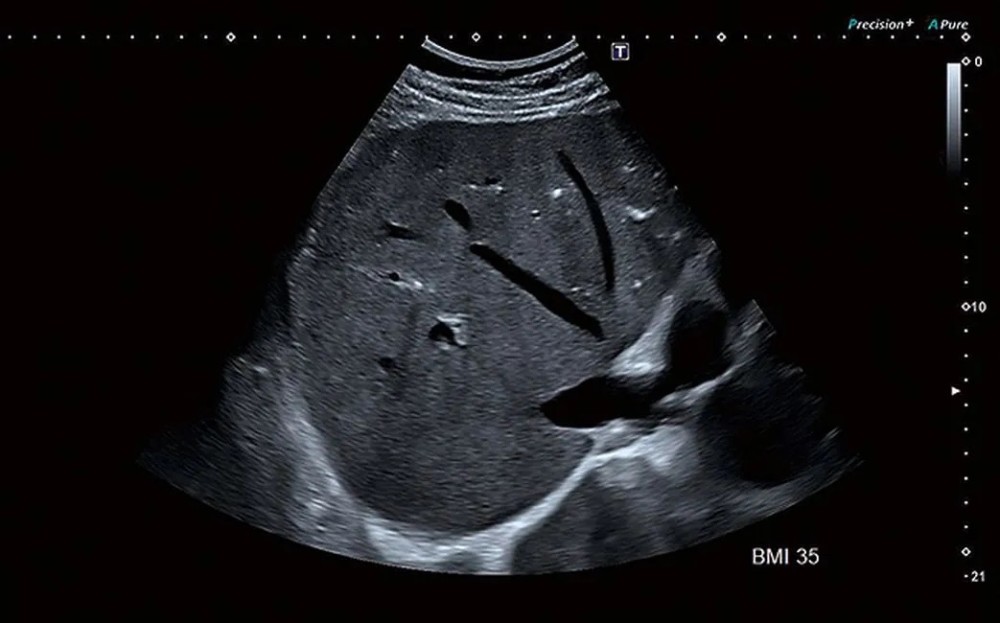

Aplio i800 ultra-genişzolaqlı problardan istifadə edir, bu problar iki ənənəvi probun əhatə etdiyi tezlik diapazonunu tək cihazda təmin edir.

Yaxın və uzaq sahələrdə yüksək həssaslıq

Daha dəqiq və aydın görüntülər